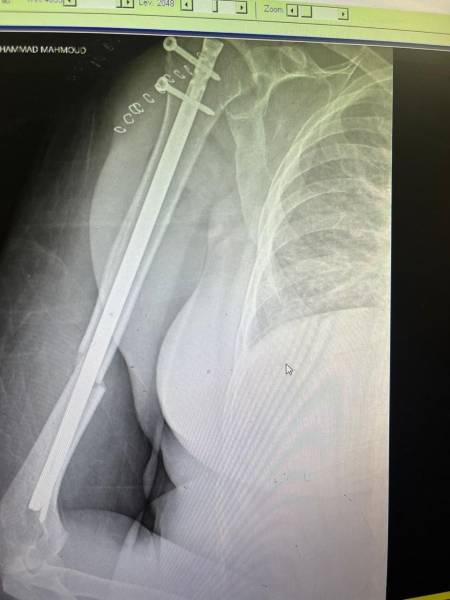

- إجراء عمليات جراحية معقدة و دقيقة في مجال العظام و المفاصل و الكسور و الإصابات ، رغم الضغط الكبير على المستشفى و أعداد المراجعين الكبيرة.

- تطبيق تقنيات جراحية حديثة و متقدمة، و ذلك في ظل التحديات التي يواجهها الفريق بسبب أعداد المرضى و المراجعين الكبيرة.